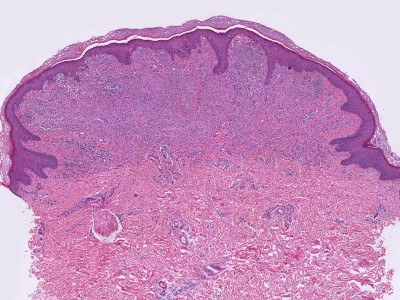

PA: Het karakteristieke PA kenmerk van Spitz tumoren

is de aanwezigheid van grote

spoelvormige cellen en/of

epithelioide cellen (melanocyten die lijken op keratinocyten).

Deze cellen zijn meestal gelegen in nesten hoog in de dermis, soms in de retelijsten

van de epidermis, soms in allebei. Er zijn verschillende histologische en morfologische

varianten van Spitz naevi, afhankelijk van welke chromosomale afwijking (tyrosine

kinase fusies, HRAS of MAP3K8 mutaties) er aanwezig is. Zie voor de correlatie

tussen de genetische afwijking, de klinische presentatie, en het histologisch

beeld het overzichtsartikel van Urso C. uit 2023.

De klassieke benigne

Spitz naevi zijn scherp begrensde symmetrische wigvormige laesies opgebouwd

uit grote junctionele (op de overgang epidermis-dermis) en dermale nesten van

spoelvormige en/of epithelioide melanocytaire cellen. Deze cellen zijn groot,

met veel bleek of matglas-achtig aankleurend cytoplasma en soms fijnkorrelig

pigment. Er is wat kern pleomorfisme, maar weinig of geen mitosen. De junctionele

nesten zijn loodrecht op de epidermis georiënteerd en vaak omgeven door spleetvormige

ruimten, dit zijn artefacten die ontstaan tijdens de bewerking van de coupe.

Melanocyten kunnen opstijgen in de epidermis (ascensie, synoniem pagetosis,

pagetoide verspreiding), meestal beperkt tot de onderste helft van de epidermis,

en transepidermale elininatie van melanocyten komt voor. Op de dermo-epidermale

overgang kunnen bij klassieke Spitz-naevi PAS-positieve eosinofiele hyaline

globuli voorkomen die

Kamino bodies worden genoemd.

Verder is er soms een perivasculair lymfocytair infiltraat. Zie ook de

ingescande

PA-coupe van de

afdeling

pathologie van de University of Toronto, en de ingescande coupes uit het

LUMC hier onder: